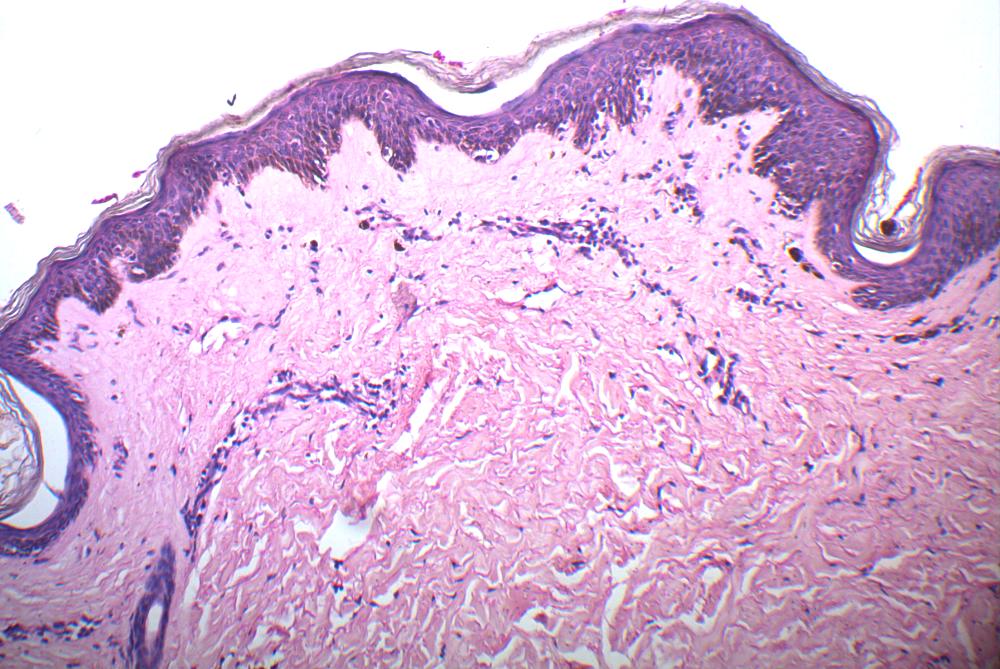

Fig 4: High power view showing hylinized collagen, lymphocytic infiltrate, melanophages and slightly atrophic epidermis with interface. (H&E, 100X)